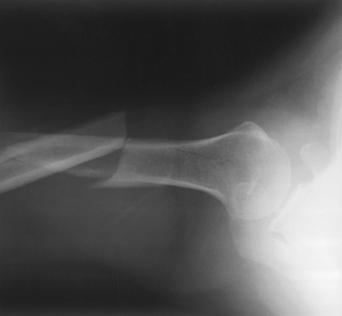

This radiographic projection is useful to show tangentially the coracoacromial arch or outlet to diagnose shoulder impingement.1,2 The tangential image is obtained by projecting the x-ray beam under the acromion and AC joint, which defines the superior border of the coracoacromial outlet.

Structures shown: The tangential outlet image shows the posterior surface of the acromion and the AC joint identified as the superior border of the coracoacromial outlet (Figs. 5-41 and 5-42).